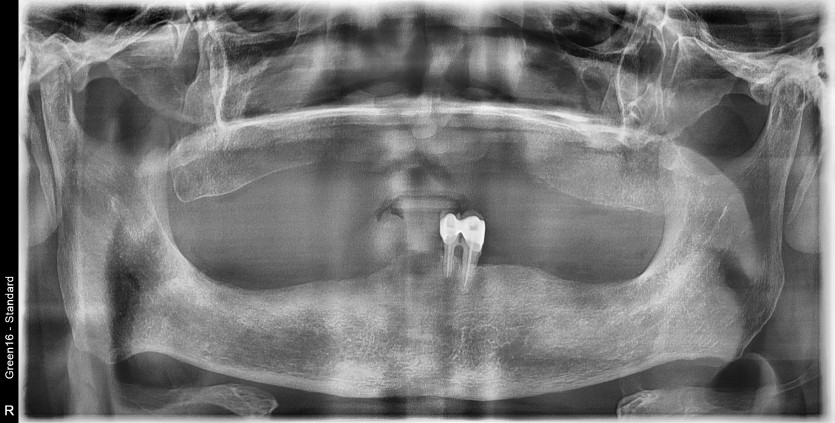

만 65세 상, 하악 전체 임플란트 증례

상,하악 전체 임플란트 증례입니다.

18개의 임플란트로 완성하였습니다.